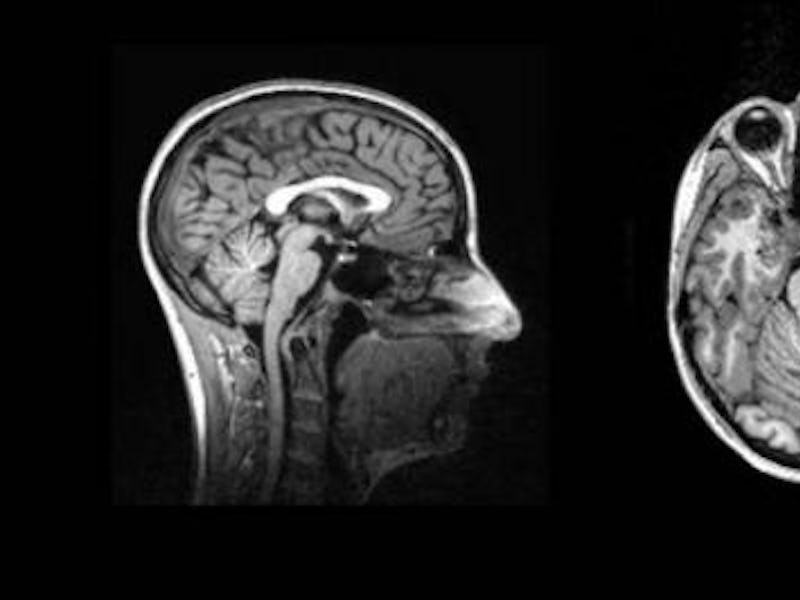

In the study, 71 participants, some from France and others from the United Kingdom, had their brain activity observed in fMRI scanners while they undertook a “pain perception task.” Everyone was sober during observation, but half of the participants were classified as binge drinkers.

The blue represents the parts of the brain that are engaged during the perception of faces, while green represents the parts engaged in the perception of bodies.

The experiment revealed the binge-drinking participants struggled more to adopt another person’s perspective. That struggle was evidenced in their brain. In the “pain-other condition,” a visual area of the brain involved in recognizing body parts showed higher levels of activation in the brains of binge drinkers only. This region is called the Fusiform Body Area (FBA).